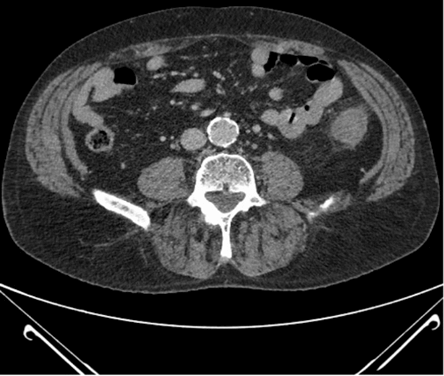

CT abdomen and pelvis with contrast showed non-specific colitis of the descending colon. Coronal and axial cuts are shown in (Figures 3 & 4). Following this, he underwent a sigmoidoscopy that showed a large mass-like ulcerated lesion in the descending colon. This involved about 15 cm of the colon and occupied about 30% of the lumen, as shown in (Figure 1). Histology was suggestive of ischaemic colitis (Figures 5-8). The multidisciplinary meeting recommended an interval colonoscopy which showed resolution of the colonic mass lesion (Figure 2). He was fluid resuscitated and started on empiric broad-spectrum antibiotics.

Figure 4: Axial post-contrast abdominal CT.